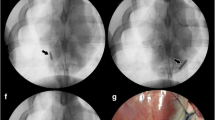

To date, the two major classes of pharmacological compounds used in clinical interventional cardiology are the mTOR inhibitors (referred to as “limus drugs”) and paclitaxel, which inhibit VSMC proliferation and migration, two key processes that contribute to neointimal thickening during in-stent restenosis (Fig. 8.3). The term “limus drugs” is confusing since pimecrolimus and tacrolimus are calcineurin inhibitors that only exhibit immunosuppressive activities and have yielded unsatisfactory results when used in drug-eluting stent platforms to prevent restenosis [129, 130]. By contrast, pivotal studies a decade ago using sirolimus- and paclitaxel-coated stents have shown a dramatic decrease of late lumen loss, the pathoanatomical correlate of angiographic and clinical restenosis, compared to uncoated bare metal stents [131]. Meta-analysis and recent clinical head-to-head trials have implicated superior performance of mTOR-inhibitor-eluting stents [132]. Interestingly, the first clinically available drug-eluting stents, Cordis’ sirolimus-eluting stent, has been unsurpassed in terms of clinical safety and efficacy as is becoming evident in recent randomized comparisons presented at large international meetings as well as peer-reviewed publications [133]. However, due to potential improvements in stent design, Abbott’s everolimus-eluting Xience V stent is the most frequently used stent in contemporary interventional cardiology.

Overview of drugs currently used on the vast majority of drug-eluting stents approved for human use. The name of the stent platform is provided in parenthesis. A large reduction in restenosis and need for target vessel revascularization has been conclusively demonstrated with drug-eluting stents that deliver mTOR inhibitors and paclitaxel, two unrelated families of drugs which cause cell cycle arrest in G0/G1-phase and M-phase, respectively. Tacrolimus and pimecrolimus are calcineurin inhibitors which only exhibit immunosuppressive properties and have yielded unsatisfactory clinical results in drug-eluting stents platforms